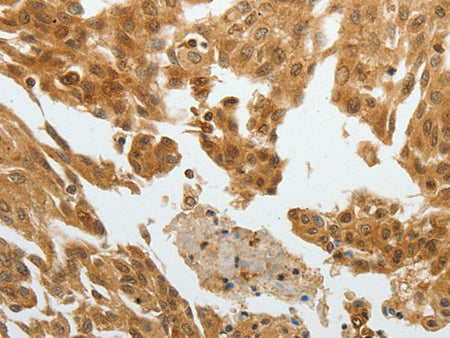

RETNLB Polyclonal Antibody Reactivity Human

Reactivity Human

Host Rabbit

Applications IHC

Research Areas Cancer,  Signal Transduction

Applications Recommended Dilution

IHC 1:50-1:200